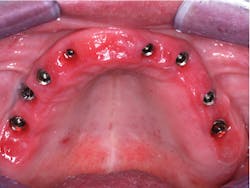

Oral hygiene—When patients with a removable prosthesis have eaten and food debris are left under the denture, they can easily clean the prosthesis in seconds by taking it out and cleaning it in their hands. Many fixed prostheses, such as the ones shown in Figures 1 and 2, cannot be cleaned well. Cleaning requires significant time and effort, and there is often not adequate access to allow cleaning under the prosthesis. The result is usually red, inflamed, and sometimes painful soft tissue (figure 3). If significant ridge lap has been necessary for esthetic reasons, such as that shown in Figure 4, the result may be not only inflamed and irritated soft tissue, but also bad breath caused by the stagnant food debris that are impossible to remove from underneath the prosthesis.

Figure 3: Same patient as shown in Figure 2. This time, the tissue is red and inflamed due to the patient’s inability to clean properly under the prosthesis.